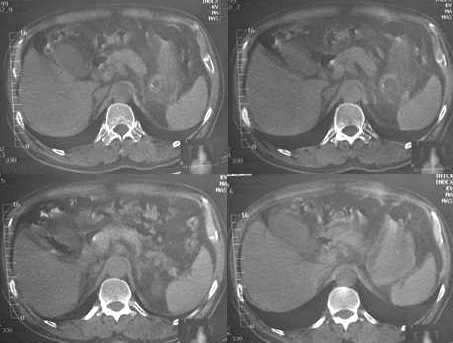

男,60岁,反复头痛,头昏,测血压最高240/120

临床怀疑嗜镉细胞瘤。做ct想了解肾上腺有无肿块。

疑问:1. 1185 1186 图 肝脏前缘低密度灶是否为腹水?ct值为-22——9.6

2.1187 图 是否为胃腔内寄生虫?还是其他呢?

3. 1167 1168 图 胆囊壁旁是什么结构?似乎不是胆囊壁增厚

3.肾上腺没有发现异常?

胆囊旁、肝脏前缘为运动伪影。胃内后方考虑肠管,建议此类检查前喝0.7%泛影葡安800ml后再扫描。